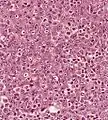

Undifferentiated nasopharyngeal carcinoma—med. power Undifferentiated nasopharyngeal carcinoma—high power

Undifferentiated nasopharyngeal carcinoma—high power Undifferentiated nasopharyngeal carcinoma—high power

Undifferentiated nasopharyngeal carcinoma—high power